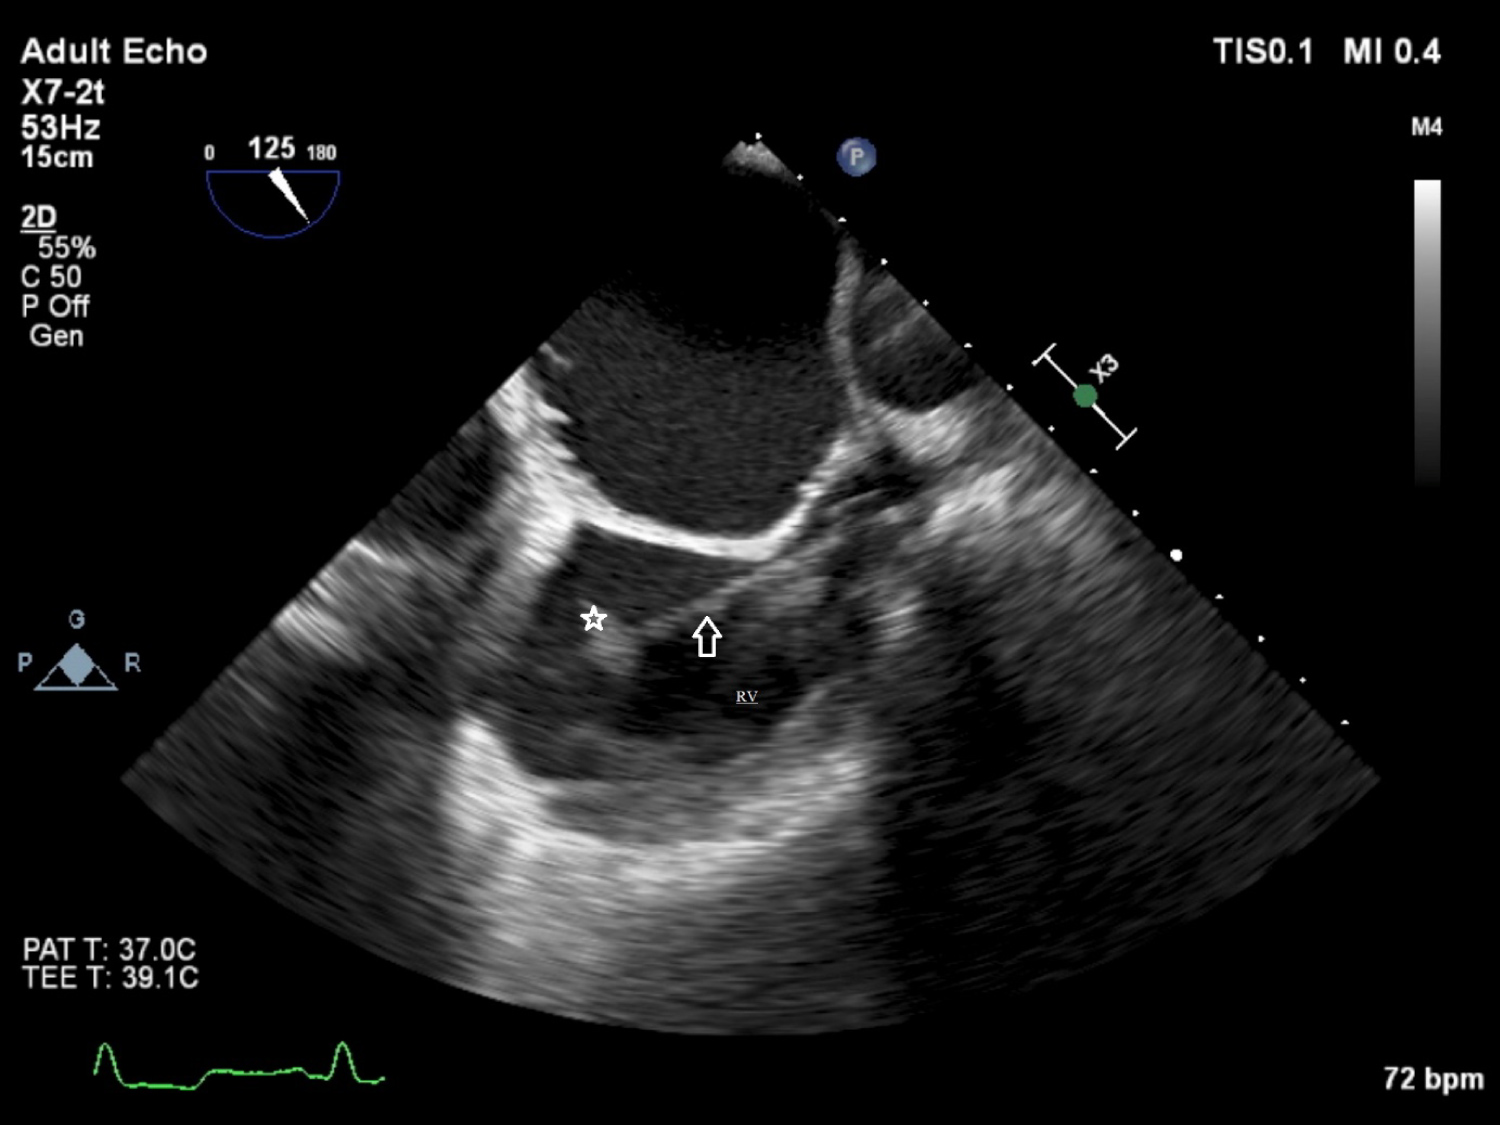

Transthoracic echocardiography (TTE) showed a mass image on the intracardiac defibrillator lead. Transesophageal echocardiography (TEE) revealed, a mobile mass resembling a vegetation on the lead, unrelated the tricuspid valve, which was 9 × 13 mm in diameter (Figure 1). The patient was hospitalized, three sets of blood cultures were drawn and vancomycin (500 mg once every three days) and meropenem (500 mg daily) were started. Blood cultures were positive for Enterobacter cloacae in two separate sets. Antibiogram showed that the microorganism was sensitive to the treatment protocol and the antibiotherapy was not changed. However, at the end of the second week of treatment, fever persisted and markers of inflammation (erythrocyte sedimentation rate [ESR] and C-reactive protein [CRP]) remained elevated. Thus, the patient was referred for transvenous lead extraction (TLE). Since the device was implanted in this patient within 1 year, lead was removed using a simple traction technique. And small vegatations on lead were detected. The culture of the extracted material was positive for Enterobacter cloacae. Antibiotherapy was appropriate according to the antibiogram and continued till the end of the postextracted sixth week.

Figure 1: Transesophageal echocardiography shows a mass (vegetation) on the lead.

RV: Right Ventriculi; Arrow: Lead of the pace; Star: Mass (vegetation) View Figure 1